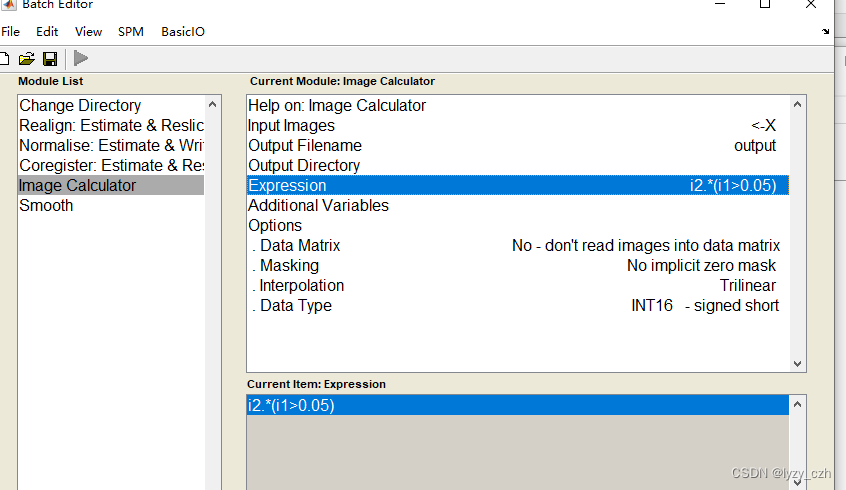

我这里的方法是使用SPM12自带的batch工具选择需要的步骤之后生成脚本文件,然后根据实际情况修改脚本完成批量预处理!

3、选择预处理步骤

选择后要点一下要输入数据的地方不然可能会报错,如下图双击Data然后回多出一行Session这样就不会有问题了

依次选择所有步骤如下一共5个步骤:

注意在Image Calculator的Expression输入是固定的因此可以直接在这里输入如下: